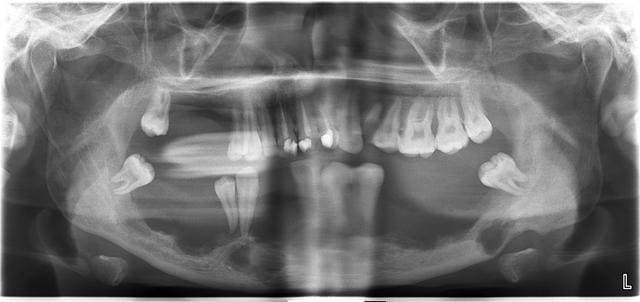

Patient de 20 ans, envoye en urgence a l hosto par son dentiste pour des douleurs aux maxillaires.

Quel est le diagnostic?

Histiocytose langerhansienne :0) maladie orpheline

Prise en charge multidisciplinaire, j en saurai plus la semaine prochaine

Douleurs continues et tres importantes. Presque impossible de faire un examen en bouche. On a une fracture de la mandibule secteur 3 qui est en train de s infecter.

Sinon on a une prise en charge multidisciplinaire avec service de cancerologie pour traitement cytostatique et prevision de consolidation de toute la mandibule par un arc.

Le probleme est la plannification de l intervention car le traitement cytostatique va faire chuter la reponse immunitaire du patient et gros risques de complications infectieuses lors de la chirurgie.